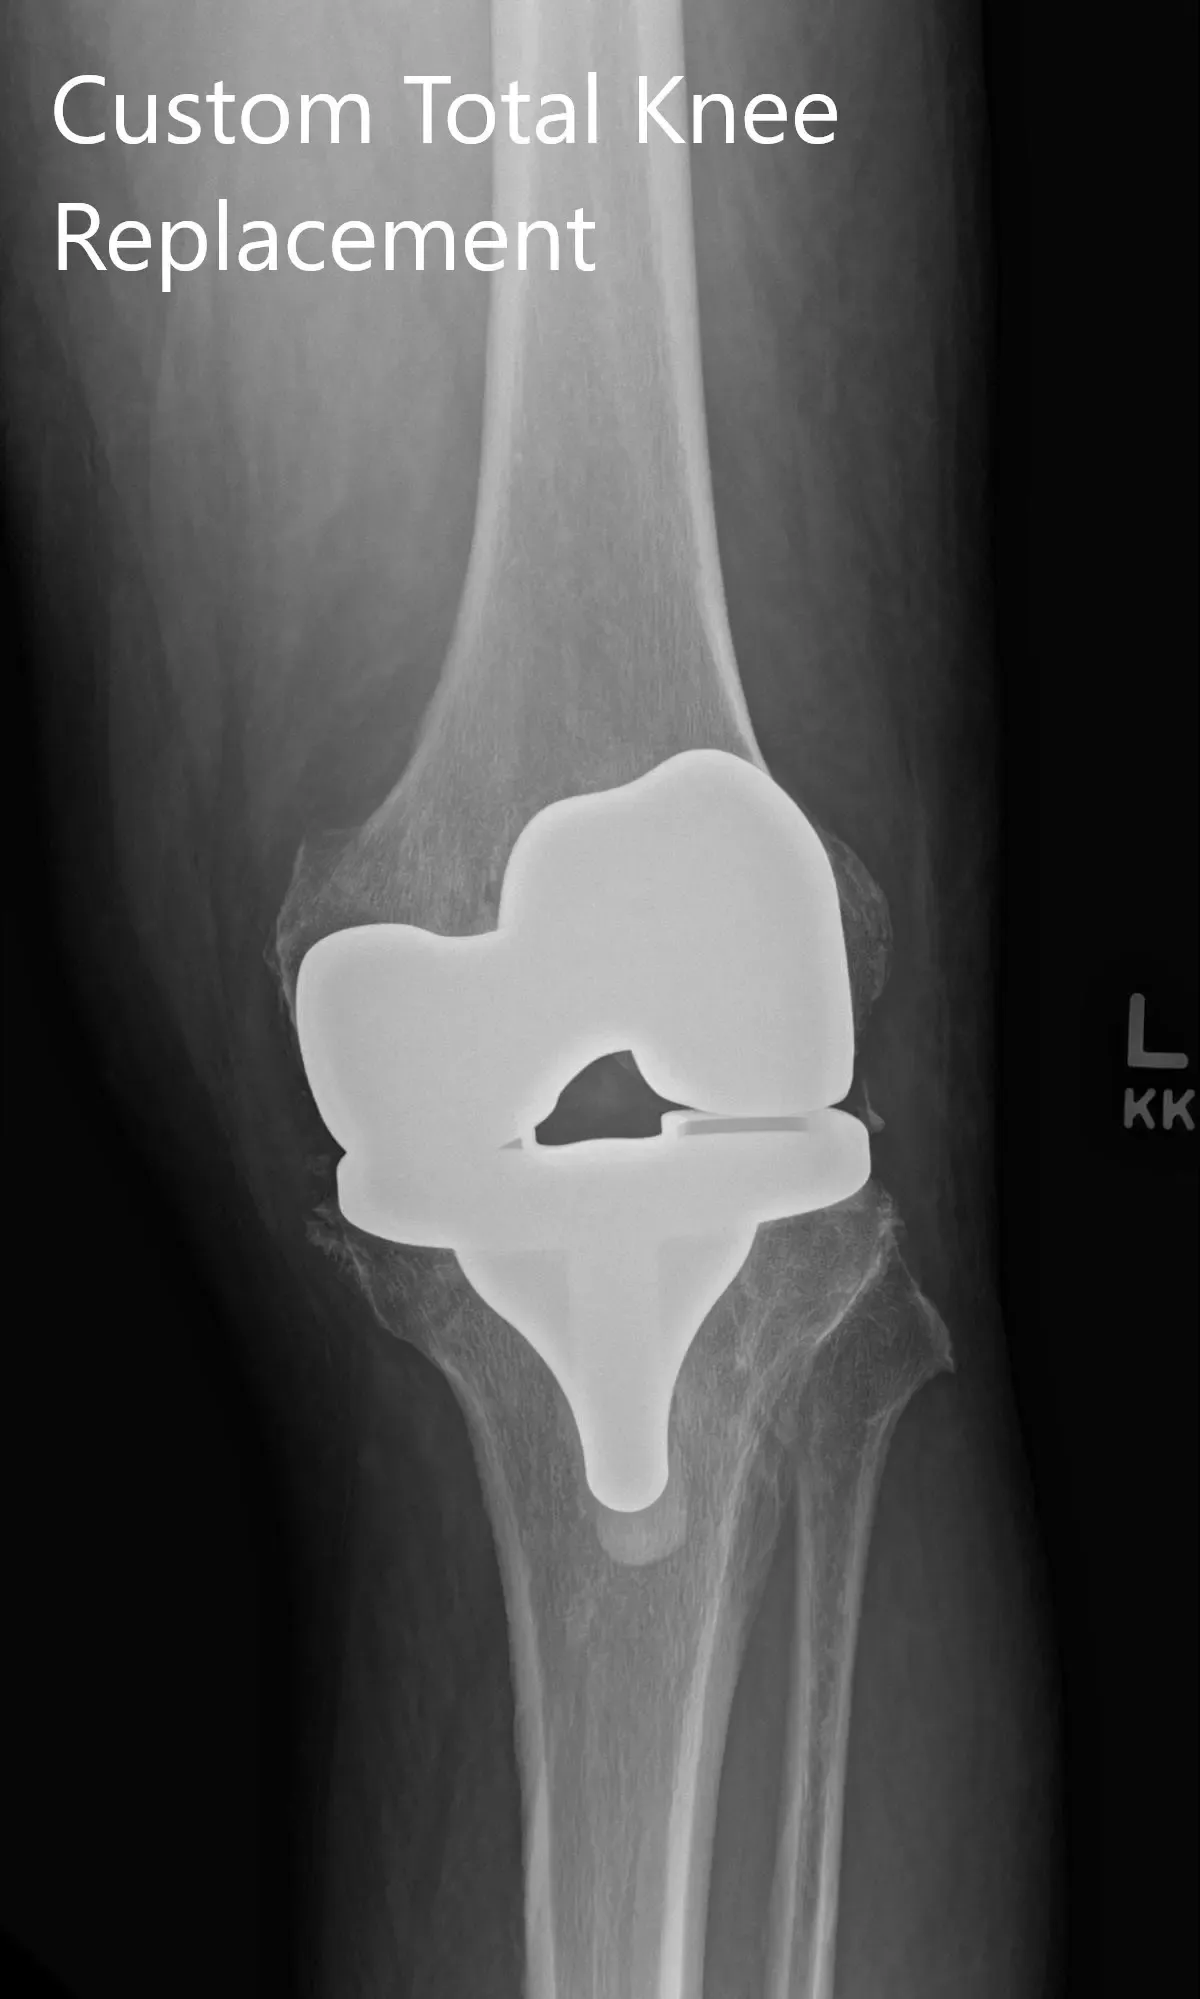

Implants used: Custom femoral implant with 6 mm polyethylene insert with a custom tibial tray with a 38 mm patellar implant.

Postoperative X-ray showing AP and lateral images of the left knee.